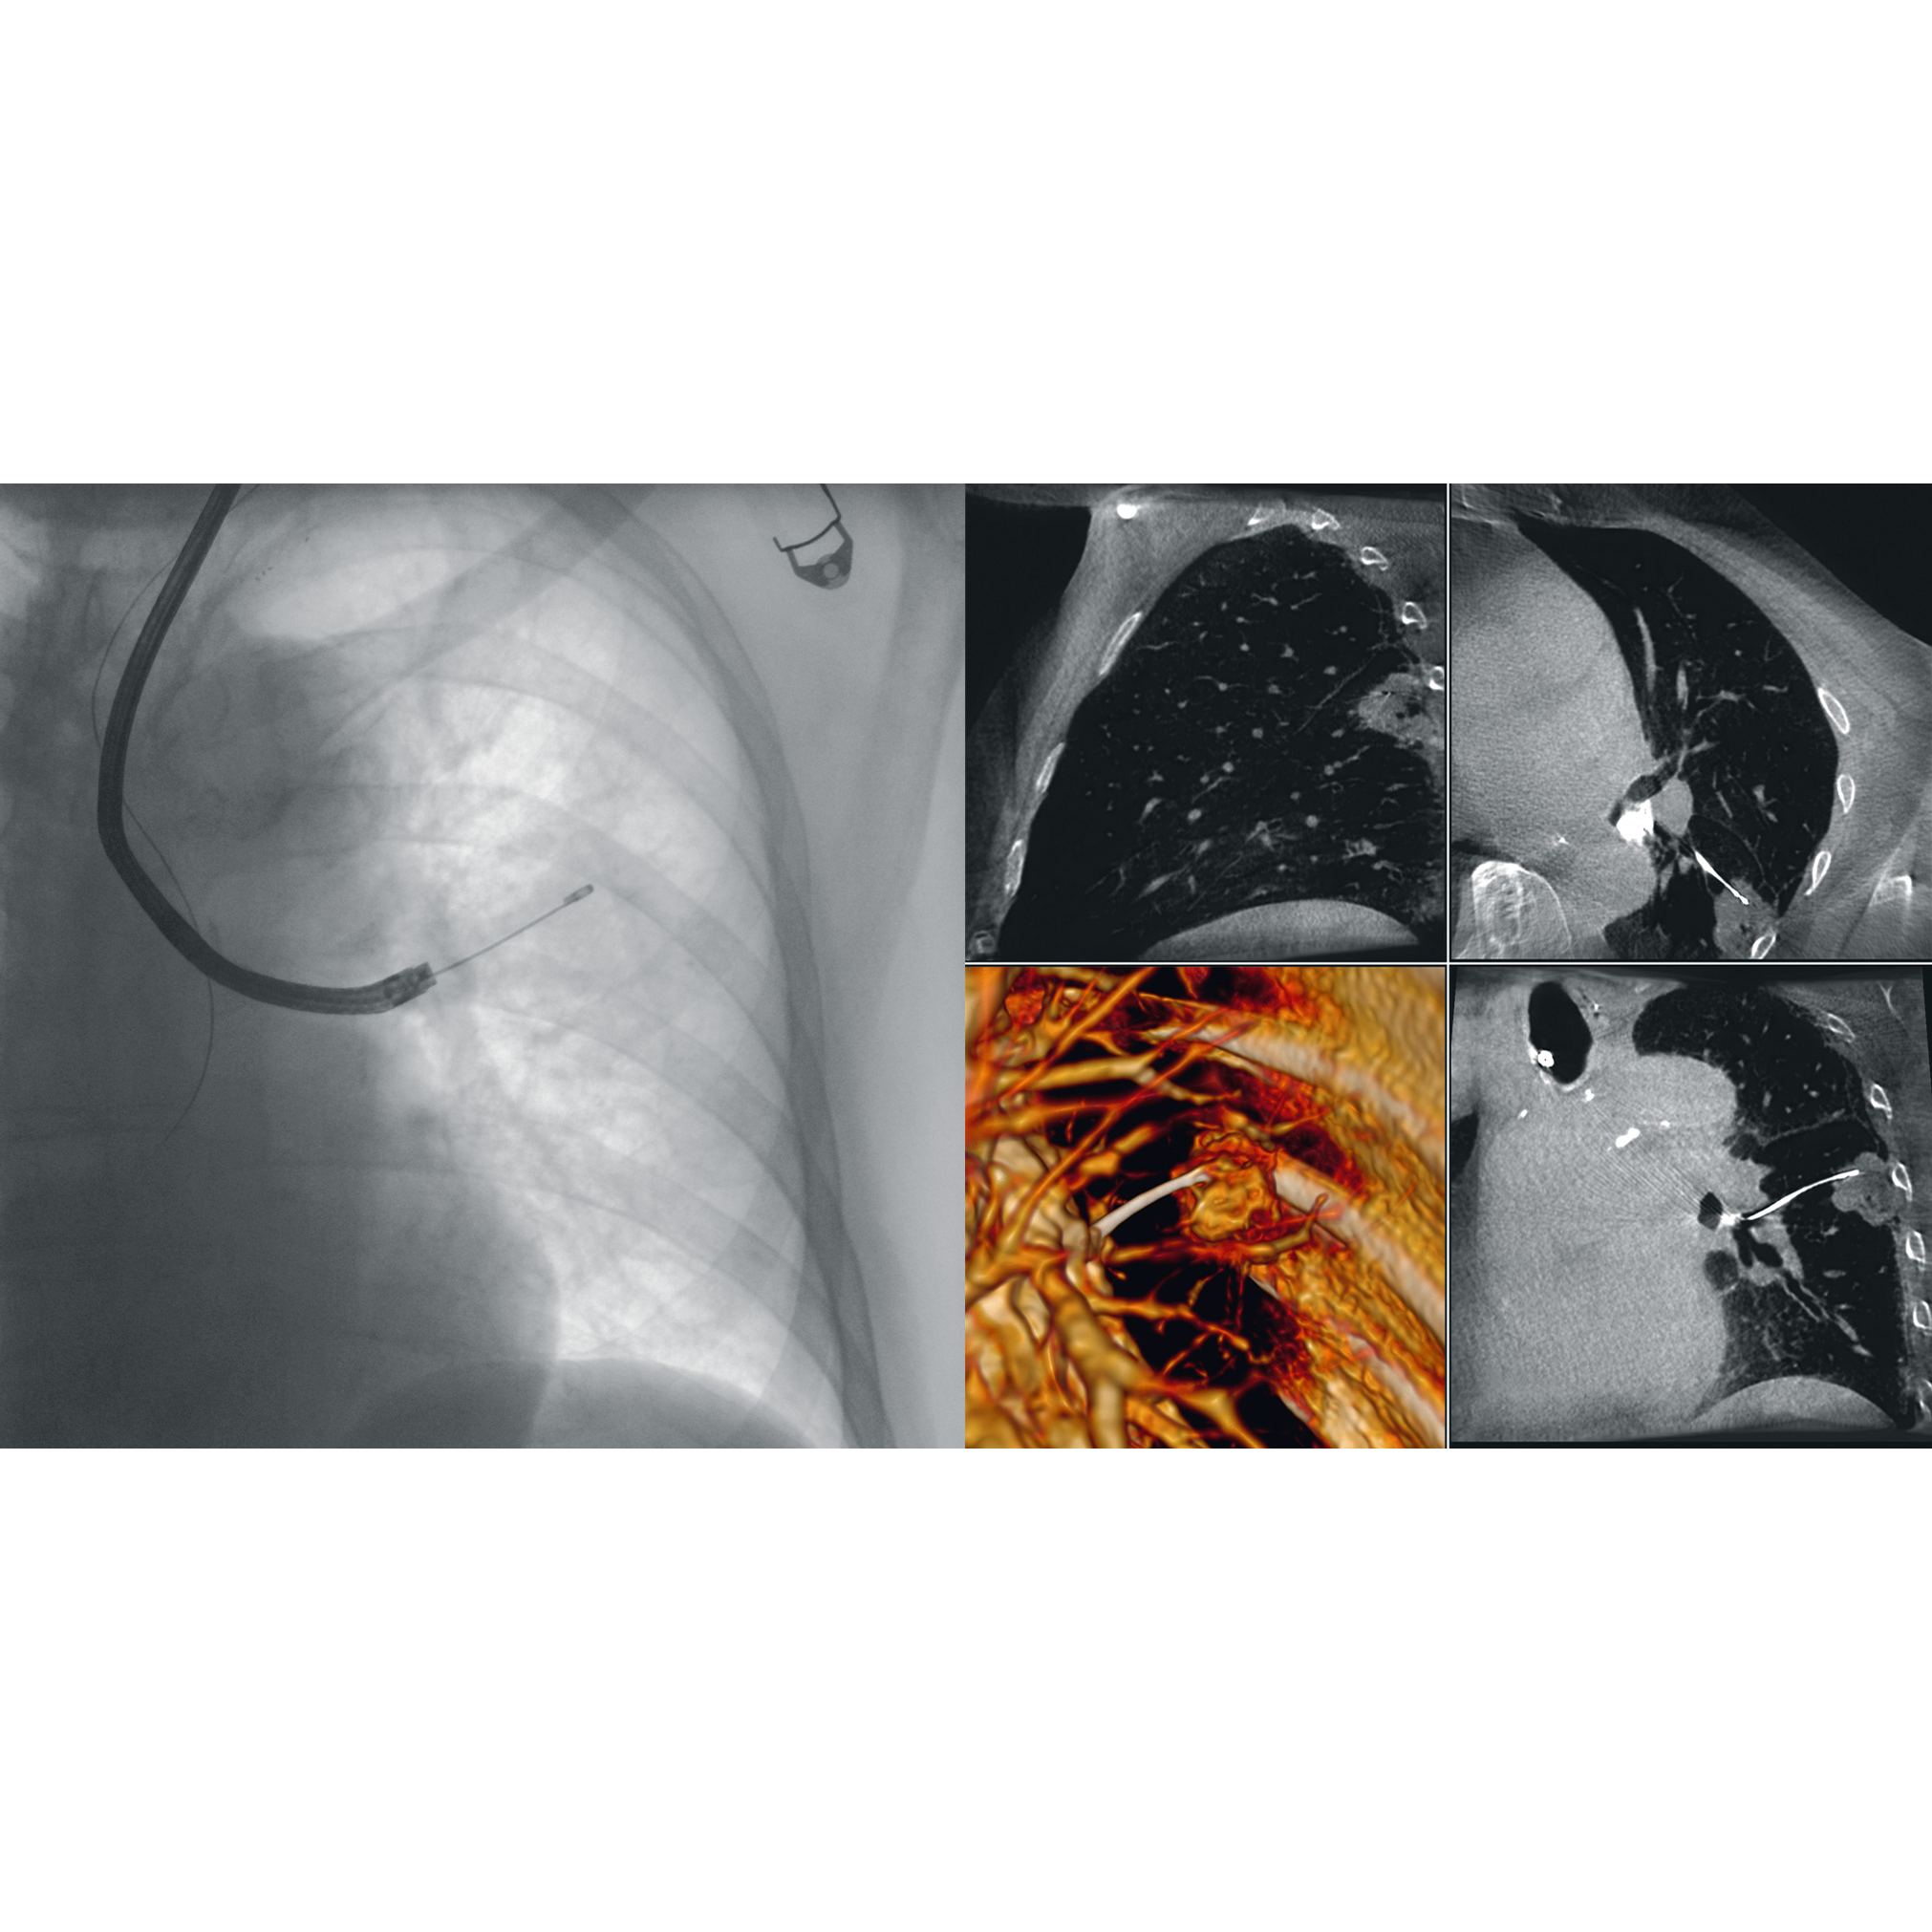

Gesundheitsdienstleister sind gefordert, die Bedürfnisse einer alternden Gesellschaft zu decken, klinische Ergebnisse zu verbessern und die Strahlenbelastung während chirurgischer Eingriffe zu verringern. Dies alles erfüllt der Ziehm Vision RFD 3D.

Er bündelt modernste CMOS-Technologie mit 2D- und 3D-Funktionen für eine verbesserte intraoperative Kontrolle.

Die patentierte SmartScan-Technologie sorgt für komplette 3D-Informationen in einem Scan. So wird der Bedarf an postoperativen CT-Scans und kostspieligen Revisionen reduziert.

Dieser mobile C-Bogen eignet sich ideal für Unfall- und Wiederherstellungschirurgie, Wirbelsäulenchirurgie, sowie für den multidisziplinären Einsatz während Hybridraum-Anwendungen.

Die besten klinischen Bilder des

Ziehm Vision RFD 3D